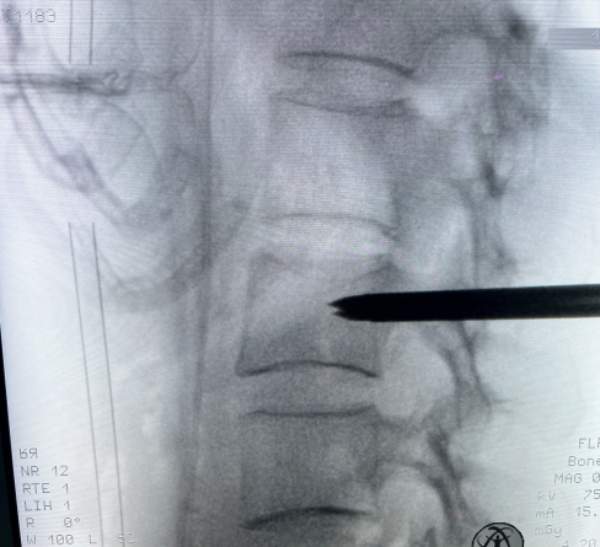

△ 穿刺到達腰2椎體內(nèi)病灶。